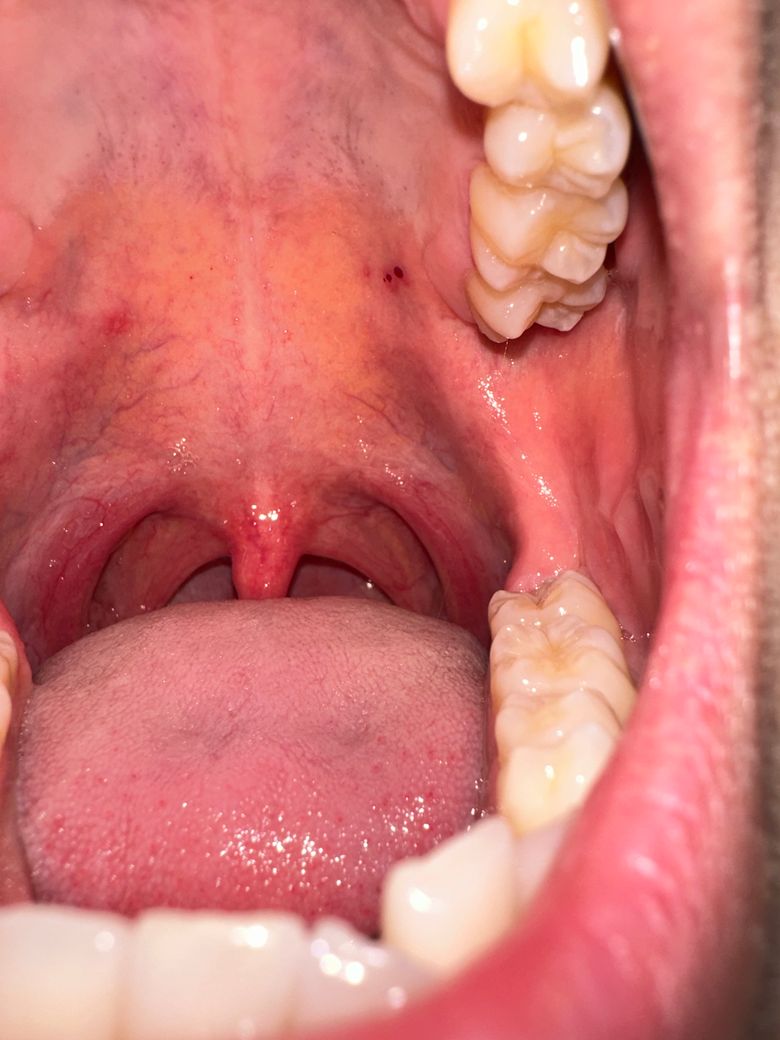

입천장에 상처나는 이것 혹시 구강암일까요?

입천장에 이유없이 상처가 나고 피가 났는데 자주는 아니더라도 일주일에 한번은 그러는것 같습니다 혹시나 하는 마음에 질문 올립니다

입천장에 그냥 상처가 생겨서 안쪽에 피가 고인거 같습니다. 시간이 지나면괜찮아 지는거니 너무 걱정은 안하셔도 됩니다.

입천장에 이유없이 상처가 나고 피가 난다고 구강암이라고 보기는 어렵습니다. 너무 뜨겁거나 맵거나 신음식을 먹거나, 거친 음식을 섭취시에 입천장이 까질수 있기에 이러한 자극감을 줄수 있는 음식은 피하는 것을 권합니다.